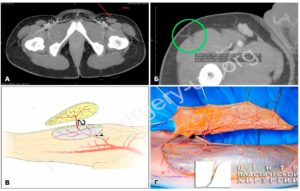

Найоптимальніший варіант реконструкції поширеного дефекту волосистої частини голови ‒ передньобічний стегновий вільний клапоть, або антелатеральний (anterolateral thigh flap (ALT)) [6,21,22]. Донорська зона може бути відносно великого розміру. Її можна використати для одномоментного закриття великого шкірного дефекту та дефекту м’яких тканин голови. Донорська ділянка ALT-клаптя розташована в естетично бажаному регіоні, який можна легко зашити лінійним швом, а у разі пересадки шкірного трансплантата ‒ приховано одягом [22‒25]. Крім того, ALT-клапоть мобілізують у надфасціальному шарі (Рис. 2), тому ще однією перевагою цього методу пластики є те, що субфасціальні структури та магістральні судини

не ушкоджуються [5,6,22]. Варіант формування клаптя в межах поверхневої фасції дає змогу сформувати тонкий клапоть, який забезпечить мінімальну морбідність у донорській зоні, та відтворити нормальний контур голови в реципієнтній зоні без додаткових коригувальних втручань.

Рис. 2. Надфасціальний шкірний ALT-клапоть з формуванням живлячої ніжки на основі перфорантної артерії. Методика забору: А – комп’ютерно-томографічне дослідження з ангіографією перфорантів передньої

поверхні стегна, які можуть бути використані як живляча ніжка острівцевого клаптя; Б – комп’ютернотомографічне дослідження з ангіографією перфорантів передньої поверхні стегна, зеленим колом обведено обраний домінантний перфорант для живлячої ніжки ALT-клаптя; В – схема забору ALT-клаптя на передній поверхні стегна (1 – низхідна гілка латеральної артерії, котра огинає стегнову кістку; 2 – шкірний перфорант низхідної гілки, котра формує живлячу ніжку ALT-клаптя); Г – інтраопераційне фото